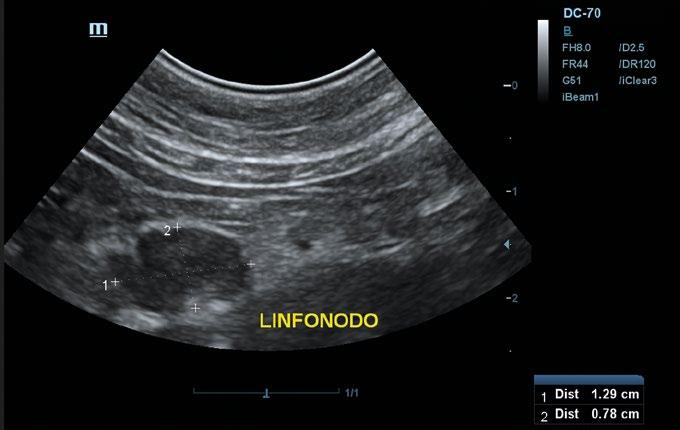

En la exploración general se observó baja condición corporal, leve grado de deshidratación y linfadenomegalia del ganglio poplíteo derecho.

La exploración dermatológica reveló la presencia de una lesión erosivoulcerativa con solución de continuidad en la zona dorsal del tarso de la extremidad posterior derecha. Los bordes de la lesión se presentaban indurados y la zona central con un exudado seroso (figura 1). Asimismo, se apreció pelo ralo y xerosis generalizada.